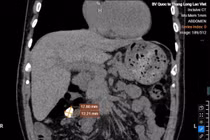

Ngay lập tức, các bác sĩ tiến hành thăm khám và chỉ định thực hiện các cận lâm sàng chuyên sâu. Kết quả chụp CT 160 lát cắt tích hợp trí tuệ nhân tạo (AI) cho biết ông M có viên sỏi to 4cm ở bể thận trái gây ứ nước độ I.

Sỏi thận 4 cm trên phim chụp - Ảnh BVCC